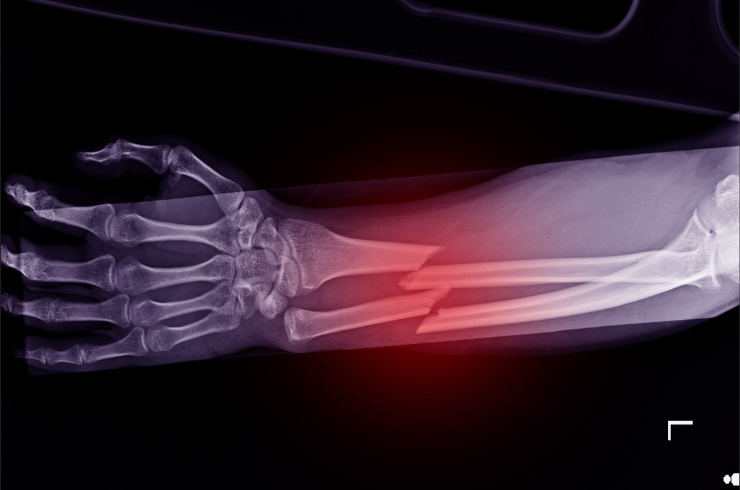

Fracture & Trauma Care

Comprehensive care for fractures and accident-related injuries, ensuring proper healing, stability, and restoration of normal movement.